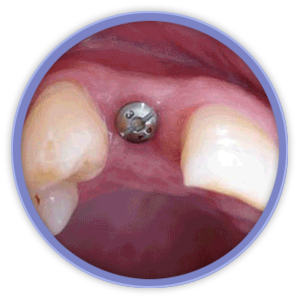

El aspecto más revolucionario en este ámbito fue la aparición de los implantes dentales que son unos pequeños bloques de titanio, con forma de raíz dental, que se insertan dentro del hueso mandibular o maxilar del paciente y sirven de sujeción para dentaduras, puentes o coronas, mejorando así la calidad de vida y aumentando las posibilidades de tratamiento de los pacientes.

Mediante técnicas de rehabilitación en un solo día, hacemos posible que el paciente salga de la consulta con los implantes y sus dientes, provisionales fijos, colocados.

La magnificación de la imagen mediante lupas o microscopio dental nos permiten niveles de acabado y de precisión mucho más exigentes. Actualmente la importancia de la estética gingival (encías), ha obligado a desarrollar técnicas de regeneración de hueso y tejidos blandos, que complementan a las cirugías de implantes entre otras.